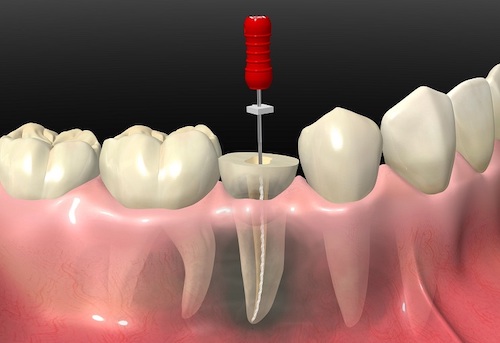

神経を取り除いた後、根管内の感染(汚染)した部分をきれいに清掃し、

MTAセメントにて根管充填を行います。そうすることで、MTAの特徴である持続的な高い殺菌力、細菌を増殖させないような状態にできます。

もちろん、根管治療がきちんと行われていなければ、MTAセメントを使用しても意味がないので、大前提治療がきちんと行われている必要があります。